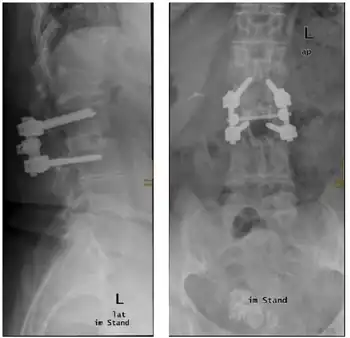

Due to the branches of the aorta that supply the anterior spinal artery, the most common causes are insufficiencies within the aorta. These include aortic aneurysms, dissections, direct trauma to the aorta, surgeries, and atherosclerosis. Acute disc herniation, cervical spondylosis, kyphoscoliosis, damage to the spinal column and neoplasia all could result in ischemia from anterior spinal artery occlusion leading to anterior cord syndrome. Other causes include vasculitis, polycythemia, sickle cell disease, decompression sickness, and collagen and elastin disorders.[1] A thrombus in the artery of Adamkiewicz can lead to an anterior spinal syndrome. This is the most feared, though rare complication of bronchial artery embolization done in massive hemoptysis.[6]

An MRI is used in the process of making a diagnosis for this condition